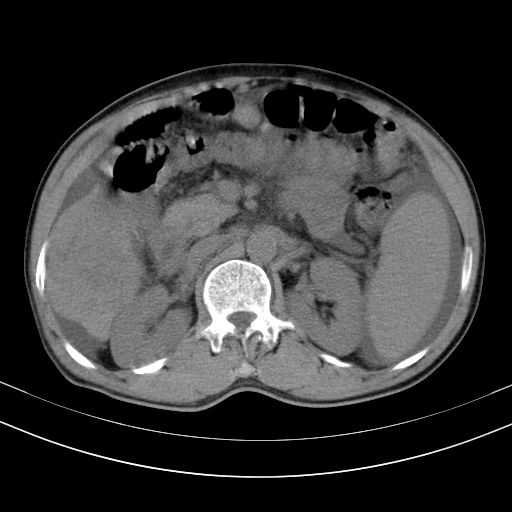

以下是引用随光逐影在2010-2-28 10:23:00的发言:[br]1)考虑肝癌;建议行ct增强扫描检查。2)肝硬化,脾大,腹水。3)慢性胆囊炎。

以下是引用dyqct在2010-2-28 16:44:00的发言:[br][quote]以下是引用随光逐影在2010-2-28 10:23:00的发言:[br]1)考虑肝癌;建议行ct增强扫描检查。2)肝硬化,脾大,腹水。3)慢性胆囊炎。